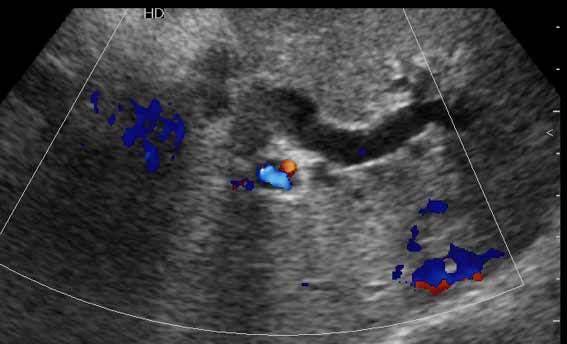

Дело в том, что в холедохе имеется нечто изоэхогенное (не знаю, видно ли это нечто на ваших мониторах). Врач УЗИ при осмотре перед поступлением в стационар на основании этой картины в заключении отметил возможность опухоли холедоха.

Гнойный холангит на фоне обструкции БДС конкрементом (камень вне скана). В холедохе определяется желчь с осадком, которая может быть ошибочно принята за его опухоль.